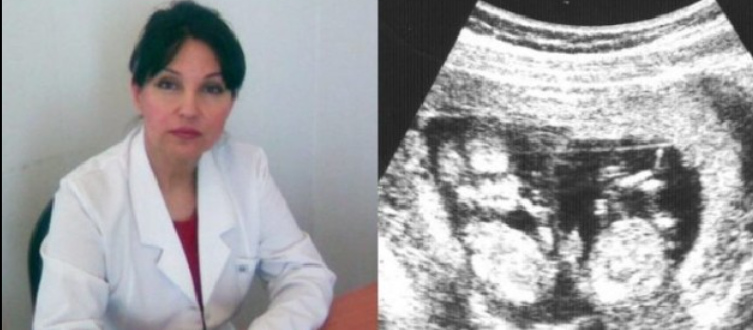

Վահանաձև գեղձի քաղցկեղ. ինչպես բաց չթողնել վտանգավոր նշանները

Վահանաձև գեղձի քաղցկեղը ժամանակին աշխտորոշելն ու դրա...